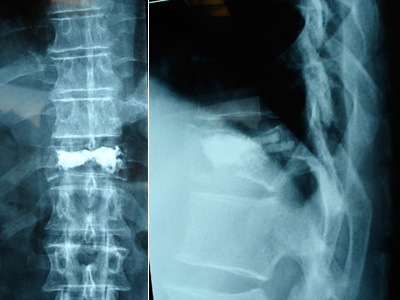

Kyphoplasty is performed under local or general anesthesia. Using image guidance x-rays, two small incisions are made and a probe is placed into the vertebral space where the fracture is located. The bone is drilled and a balloon, called a bone tamp, is inserted on each side. These balloons are then inflated with contrast medium (to be seen using image guidance x-rays) until they expand to the desired height and removed. The spaces created by the balloons are then filled with PMMA, the same orthopedic cement used in vertebroplasty, binding the fracture. The cement hardens quickly, providing strength and stability to the vertebra, restoring height and relieving pain.

Both vertebroplasty and kyphoplasty utilize a cement-like material that is injected directly into the fractured bone. This stabilizes the fracture and provides immediate pain relief in many cases. Kyphoplasty has the additional advantage of being able to restore height to the spine thus reducing deformity. After either procedure, most patients quickly return to their normal daily activities.